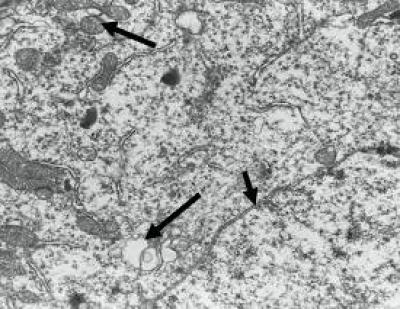

Heroin abuse can damage many brain areas, including the pedunculopontine tegmental nucleus of the midbrain, the ventral tegmental area, and nucleus accumbens. Persistent use of heroin induced irreversible damage to the nervous system. To verify the relationship between acupuncture, neurotrophic factor expression and brain cell structural changes, a research team from Anhui University of Chinese Medicine in China established a rat model of heroin relapse using intramuscular injection of increasing amounts of heroin. During the detoxification period, rat models received acupuncture at Baihui (DU20) and Dazhui (DU14). Rongjun Zhang and co-workers from this team found that the structure of the ventral tegmental area in heroin relapse rats gradually became normalized after acupuncture treatment, and the expression of brain-derived neurotrophic factor and glial cell line-derived neurotrophic factor also increased in the ventral tegmental area following acupuncture. These results, published in the Neural Regeneration Research (Vol. 9, No. 3, 2014), suggested that acupuncture at Baihui and Dazhui protected brain neurons against injury in rats with heroin relapse by promoting brain-derived neurotrophic factor and glial cell line-derived neurotrophic factor expression.

Article: " Normalization of ventral tegmental area structure following acupuncture in a rat model of heroin relapse," by Rongjun Zhang1, Xinghui Cai1, Xiaoge Song1, Chaoyang Dong2, Xiaorong Hou1, Lei Lv1 (1 Anhui University of Chinese Medicine, Hefei, Anhui Province, China; 2 Anhui Academy of Medical Sciences, Hefei, Anhui Province, China)

Zhang RJ, Cai XH, Song XG, Dong CY, Hou XR, Lv L. Normalization of ventral tegmental area structure following acupuncture in a rat model of heroin relapse. Neural Regen Res. 2014;9(3):301-307.